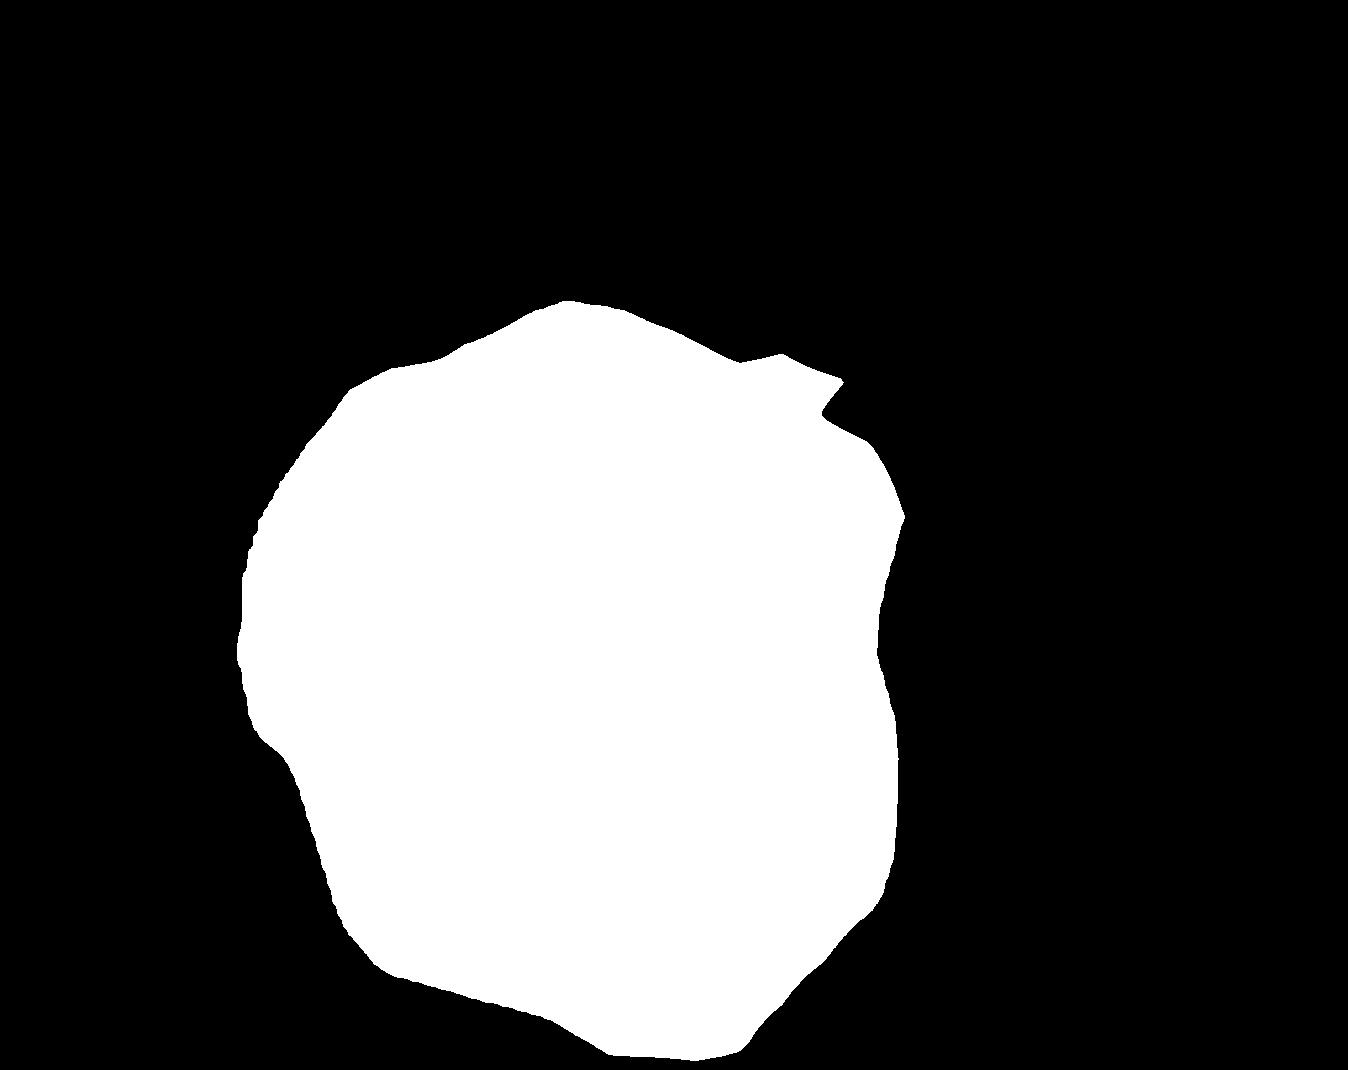

Figure 4 shows some example masks predicted by our best performing model (DivergentNets) together with masks produced by the intermediate models. We see that each intermediate model learns slightly different features, making an overall more precise segmentation mask when combined. For example, the first row of Figure 4 shows the predicted masks and ground truth of a large polyp. We see that each model predicts slightly different masks for the same input and that TriUNet over-estimates the size of the polyp. After averaging the predicted masks for DivergentNets’ final output, this area is smoothed out by the predictions from the other intermediate models.

Even though DivergentNets primarily produces more accurate masks than any single model, there are cases where masks from the intermediate model better match the ground truth. We see this in row three, where DeepLabv3+ produces a more precise mask than all other intermediate models, making the averaged output less accurate.